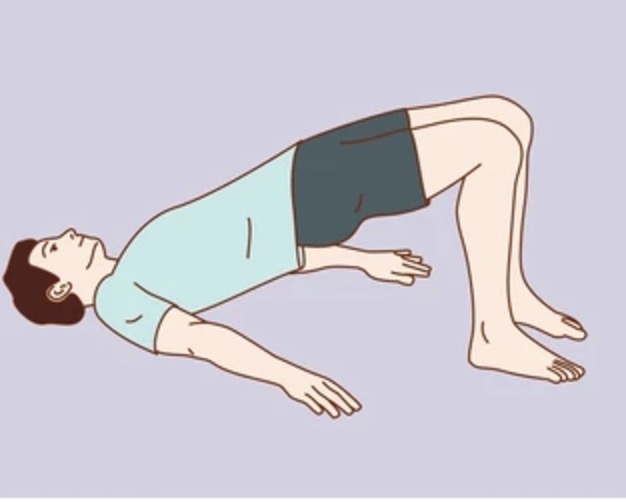

추운 겨울철에도 실내에서 안전하게 할 수 있는 관절 운동을 소개합니다:

- 앉았다 일어나기 운동 (하루 10회씩 3세트)

- 다리 들어올리기 (각 다리 15초씩 유지)

- 무릎 굽혔다 펴기 (20회씩 3세트)